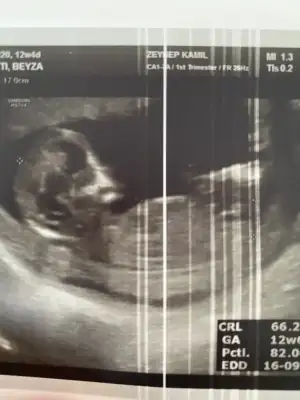

Merhaba arkadaşlar devlet hastanesine gittim bugün 11+1 di ikili tarama testi için Aslında haftaya özele de gidicem 12+3 olacak o zaman da kan vericem. Devlet özel birlikte götürüyorum. İyi görünüyor dedi doktor devlette olunca çok da bişey soramıyorsun . Başından beri erkek hissediyorum ama cinsiyet tahmini yapacak arkadaşlar varsa çok sevinirim. Herkese sağlıklı günler

Nub göremedim ama alnı çenesi kız gibi kafa yapısı erkek gibi. Hiç bilemedim o yüzden. Bende senin gibi devlet özel birlikte gidiyorum 2 haftada bir dönüşümlü. Ama şansıma özelden devlete geçen bi doktor buldum. Soru sormayı bırak soracağın merak ettiğin aklına takılan bişey var mı vs diye soruyor sürekli detaylı uzun uzadıya cevaplıyor. Umarım doğuma kadar diğer devlet doktorları gibi olmaz 😄

Cinsiyet tahmini yapan arkadaşlar bakabilir misiniz? Doktor %90 bir şey söyledi ama önceki doktor da başka bişey dediği için size sormak istiyorum. 12+6